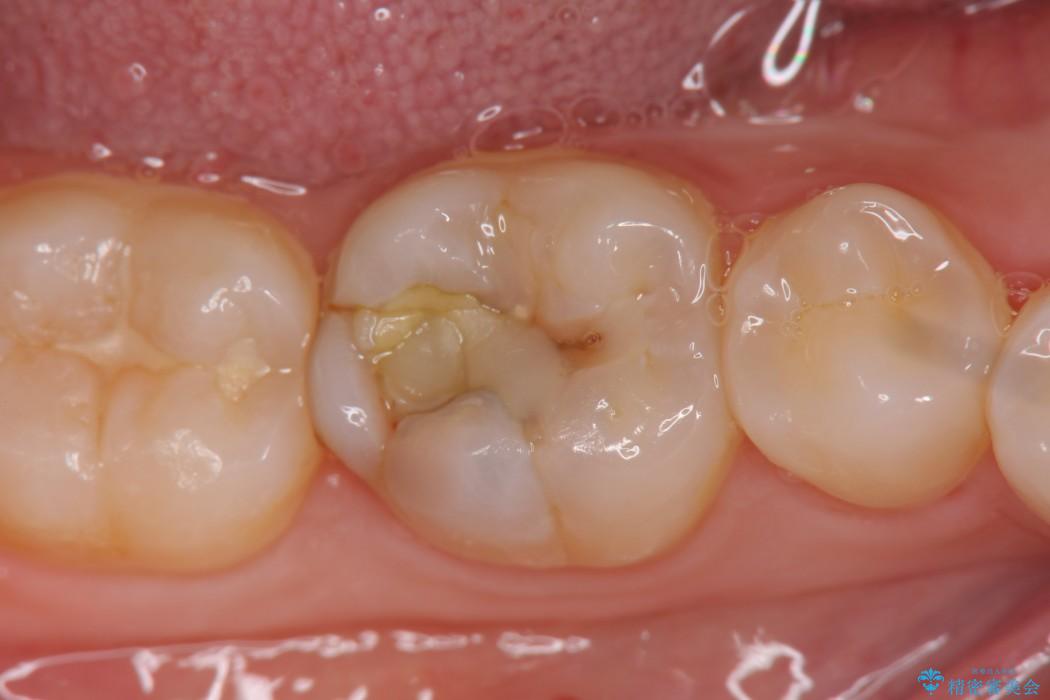

黒ずんでいる歯が気になりご来院されました。

診査をした結果、顎左右の前から6番目の歯に深い虫歯があったため、詰め物(インレー)タイプで修復していく(e-max プレスインレー)での治療を行いました。

今回は歯の黒ずみを気にしてご来院されましたが、診査をしますと神経の治療が必要になる一歩手前の状態である神経の近くまで虫歯が広がっていました。

早めの治療を行えたことにより詰め物での治療にて治すことができました。